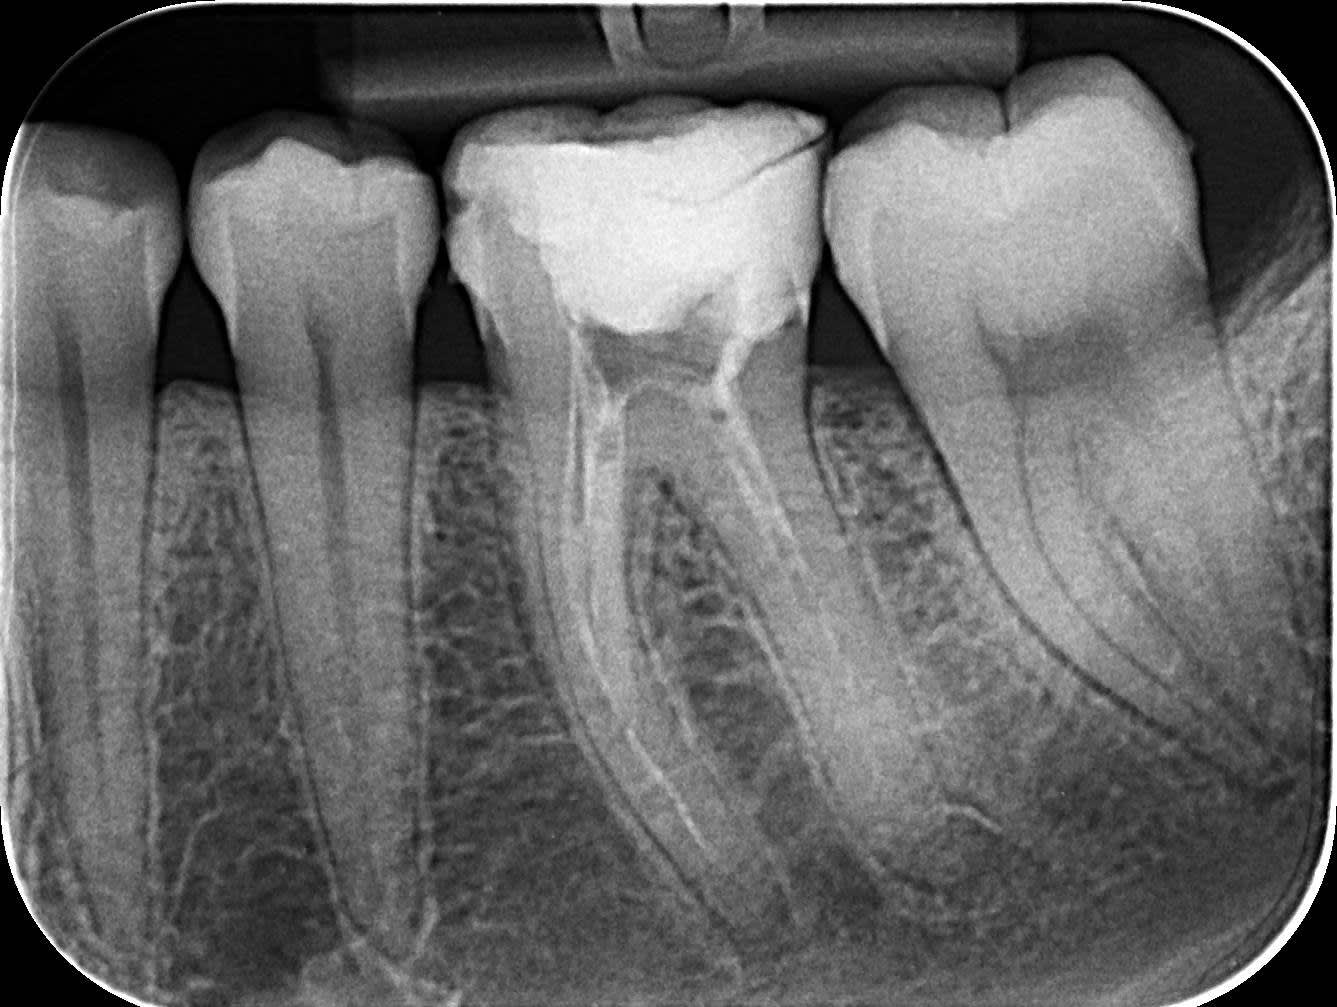

Resultat de mon endo

Lime endomoteur casse MV :s

Et finalement en distal c'était surement de l'hydroxyde de calcium car ça a plus ou moins disparu !!

(2seances d'hydroxyde de calcium, chaque seance irrigation Hypo, toujours sous digue, d'où la décision de laisser la Lime en place, la patiente est informée et rassurée)

Obturation composite direct